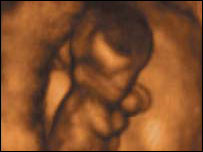

ہاتھوں کے استعمال کا رجحان پیدائش سے پہلے شروع ہوجاتا ہے

ماں کے پیٹ میں دس ہفتے کے بچے میں جس ہاتھ کو استعمال کرنے کا رجحان ہوگا وہی ہاتھ وہ ساری عمر استعمال کرے گا۔

دس ہفتوں کا بچہ انگوٹھا چوسنے کے لیے بہت چھوٹا ہوتا ہے لیکن وہ اپنا ہاتھ ہلا سکتا ہے اور پتا چلا کہ پیدائش سے پہلے بچوں کی اکثریت دائیں بازو کو ہلاتے ہیں۔